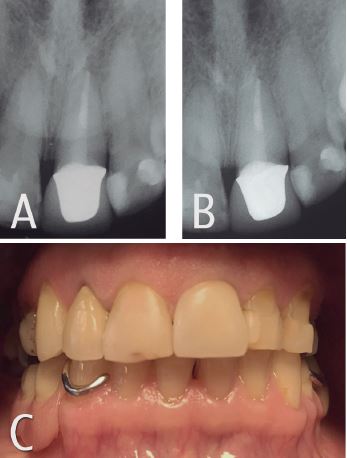

En la fase rehabilitadora, se confecciona poste de fibra de vidrio individualizado, que consiste en un poste de fibra central ajustado íntimamente con resina compuesta a la anatomía interna del canal radicular (Figura 3). Cementación definitiva de poste con Relyx U200 (3 M ESPE®, St. Paul, MN, EE. UU.). Se decidió observar la evolución del tratamiento por 4 meses mediante la restauración con una prótesis fija unitaria de carácter provisorio. Pasado este periodo se confeccionó una prótesis fija unitaria metal cerámica de carácter definitivo y se cementó con cemento resinoso Relyx U200 (3 M ESPE®, St. Paul, MN, EE. UU.) (Figura 3).

En los controles clínicos y radiográficos de 6, 12 y 24 meses la paciente se encontraba asintomática y radiográficamente se observaron signos de salud periodontal pudiéndose catalogar de exitoso el tratamiento (Figura 4).